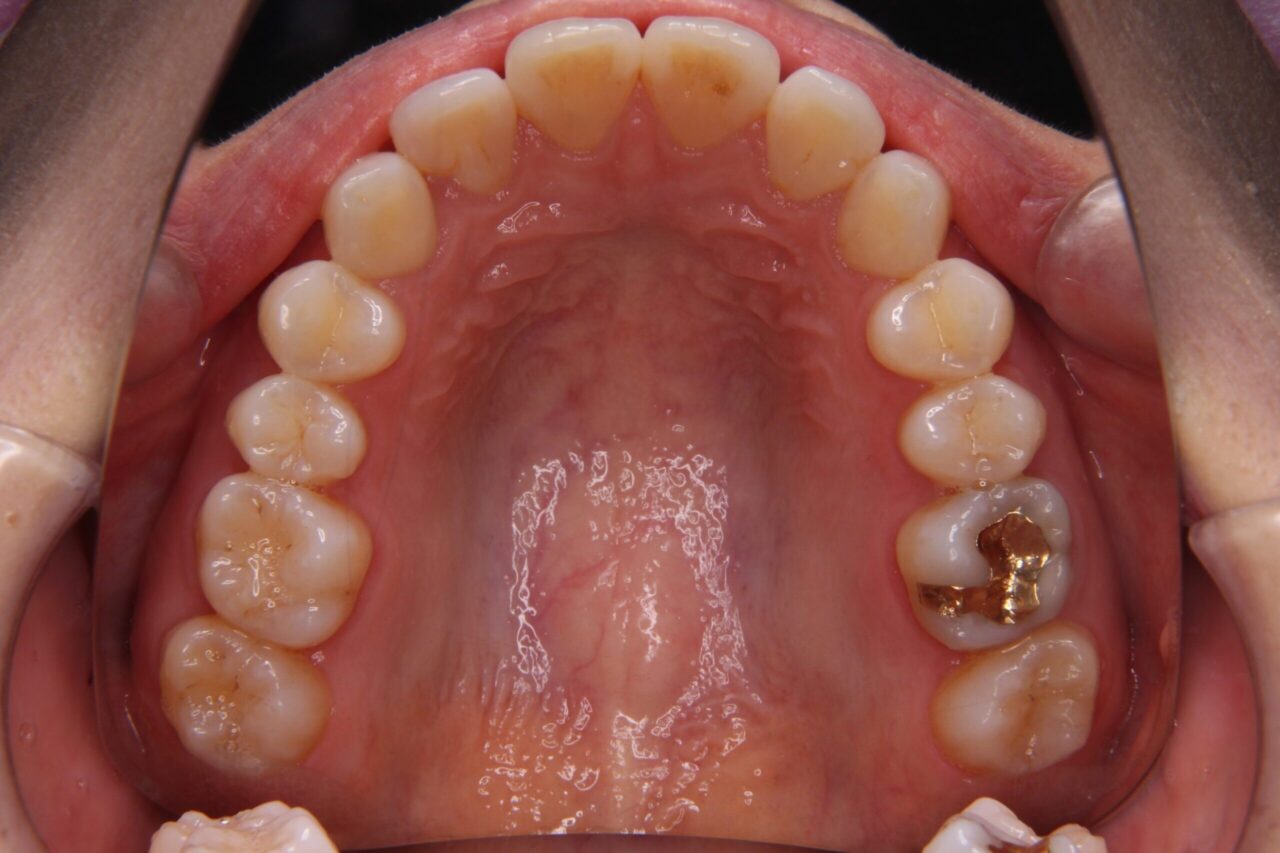

矯正後の歯列

矯正後の歯列がこちらです↓↓↓